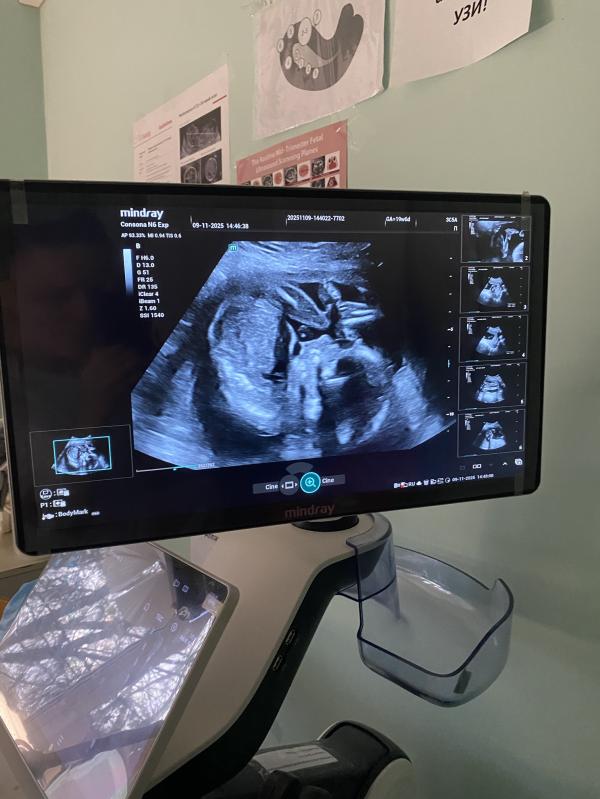

Прошли мы вчера второй скрининг…

У нас будет второй сын!😄